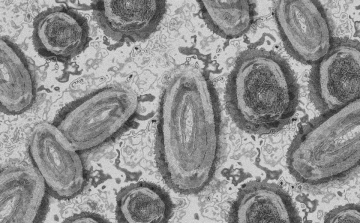

Tovább nőtt a majomhimlő-fertőzöttek száma Magyarországon

Újabb két embernél igazolt majomhimlő-fertőzést a Nemzeti Népegészségügyi Központ (NNK) a 33. héten - augusztus 15-től 21-ig -, ezzel 64-re nőtt a magyarországi esetek száma.

Meghaladta a 13 ezret a majomhimlő-fertőzöttek száma az Egyesült Államokban, a legtöbb esetet Kaliforniában és New York államban regisztrálták.

Megfertőződött a majomhimlővel egy gyerek Németországban

Megfertőződött majomhimlővel egy négyéves kislány Németországban - jelentették kedden német hírportálok az országos közegészségügyi intézet (RKI) adatai alapján.

Újabb kilenc, 23-50 éves férfinél igazolták a majomhimlő-fertőzést Magyarországon, ezzel 42-re nőtt a fertőzöttek száma - közölte a Nemzeti Népegészségügyi Központ (NNK) csütörtökön az MTI-vel.

Tovább nőtt a majomhimlő magyar fertőzöttjeinek száma

Újabb hat embernél diagnosztizálták a majomhimlő vírusát, így harmincra emelkedett az igazolt fertőzöttek száma Magyarországon - közölte a Nemzeti Népegészségügyi Központ (NNK) pénteken az MTI-vel.